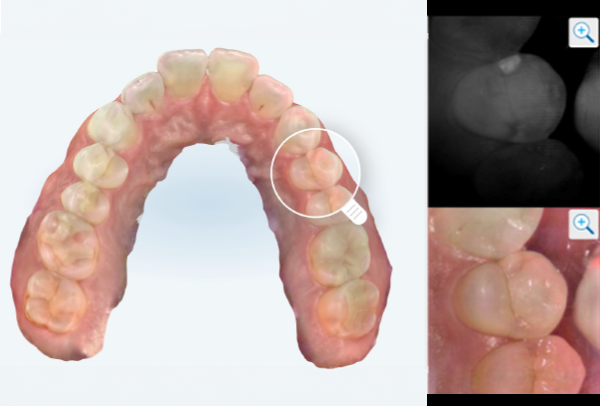

インレー症例

初診時パノラマ

初診時口腔内写真

iTero NIRI機能による診査

虫歯除去後

初診時バイトウィングデンタル

レントゲンだとちょっと虫歯が怪しいくらいに写っている。これだけだと確定診断としては、判断材料が少ないと考えられる。

黄色丸の部位が、他の部位と違って白く抜けがあるのがわかります。これがNIRI機能による虫歯の診査です。

この機能のおかげで、歯と歯の間の見つけにくい虫歯がよくわかるようになってきました。

In(インレー)セット後

当院では自費のインレー(つめ物)の場合、ゴムのシートをかけてから詰めていきます。

ゴムのシートをすることで、歯面を最大限乾燥することができ、接着力が上がる他、操作時の材料の誤飲の防止、接着剤の歯肉縁下(歯ぐきの中)への侵入を防止するなどといったメリットがあります。(歯の並びによっては、ゴムのシートができないことがあります。また、シートをかけることで苦しくなる、苦手という方には無理に行いません。)

年齢・性別 40代・男性

主訴 左上の奥歯がしみることがある

治療内容 左上4の虫歯

治療期間 2週間

リスク・副作用 虫歯の大きさによっては、神経をとらないといけなくなることがあります。

また、虫歯が大きかったケースで神経を残した場合、治療後にしみるなどの

症状が続くことがあります。

費用 ・ジルコニアインレーで修復

55,000円

治療方針

IOSのNIRI機能によって虫歯部分が明らかになったので、虫歯を除去後に修復治療を行うこととしました。

特記事項

ラバーダムは歯とつめ物をくっつける際に非常に効果的です。

人間は呼吸をしますので、お口の中はかなり湿度が高くなっています。水が多い状態でものをくっつけようと思ってもなかなかくっつかないということと同じになります。

ですので、呼気中の湿度に左右されないようにするために、ラバーダムを用いて接着力を高くしています。

ラバーダムで息が苦しくなる場合は使用しませんし、ラバーのアレルギーがある場合も使用できません。

担当医師所見

虫歯の有無を確認する上で今まではレントゲンと自分の目での確認でした。現在は目で見るよりもはるかにわかりやすいIOSという装置がありますので、虫歯の発見がしやすくなりました。

そのため、患者さんの虫歯の進行の段階が早いうちにわかる様になり、神経をとらなければならないというケースが非常に少なくなっています。